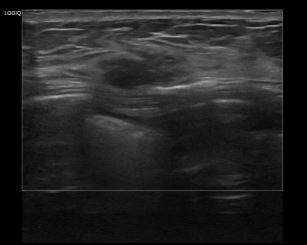

상기환자는 유방암 추적관찰 위해 내원하신 40대 초반 여성분으로 의심스러운 우측 혹 조직검사 시행해 유방암 진단되었습니다.